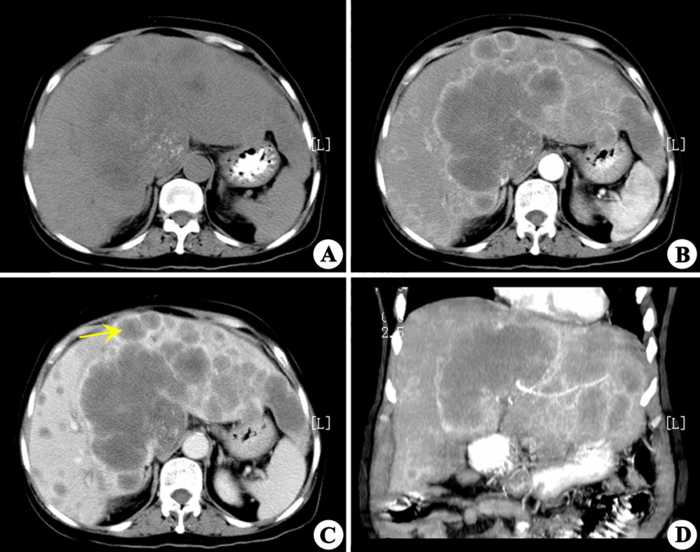

大肠癌伴肝转移

注 A:CT平扫;B:CT增强扫描的动脉期;

C:CT增强扫描的肝实质期;D:CT增强扫描的冠状位图像。